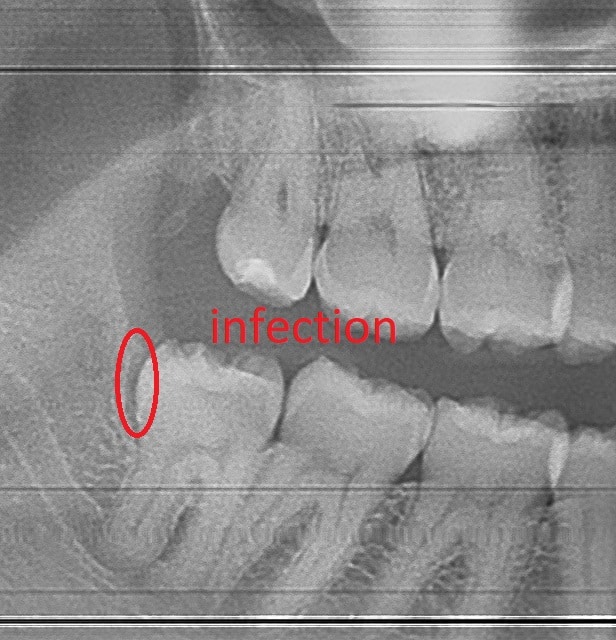

When Tooth decay extends deep under the gum, the tooth is cracked, severe periodontal disease is present, or a tooth infection cannot be resolved a tooth extraction is recommended as the best option.  Tooth pain caused by a broken or infected tooth is a dental emergency which may require a tooth extraction to resolve.

The best way to determine if a tooth needs to be extracted is to visit your dentist for an accurate diagnosis.  When a tooth is required to be extracted it maybe infected causing pain and/or swelling.  Dental x-rays are required to determine the extend of the tooth damage.  Some very infected and painful teeth can be saved with a root canal and a porcelain crown.  Upon careful examination, the dentist can determine if your tooth can be saved.

Antibiotics are not always necessary for a tooth extraction.  In the presence of  a large infection, facial swelling, or an abscess the dentist may decide to prescribe antibiotics to help treat the infection after the tooth removal.   Most of the infection is often removed along with the infected tooth.   Following the tooth extraction your dentist will also manually clean the empty socket and irrigate it with saline.  To be extra cautious antibiotics can be prescribed to kill the rest of the bacteria causing infection.  Some patients will experience a short fever for 12-24 hours and may have swollen lymph nodes as the bacteria spreads after the tooth extraction and the body attempts to fight off the bacteria.